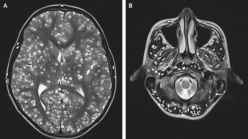

Cisticercos en el encéfalo